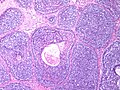

Adenoid cystic carcinoma of the breast

Adenoid cystic carcinoma of the breast. H&E stain. | |

Adenoid cystic carcinoma of the breast is a rare type of breast cancer that is similar to a relatively common tumour of the salivary gland.

Microscopic